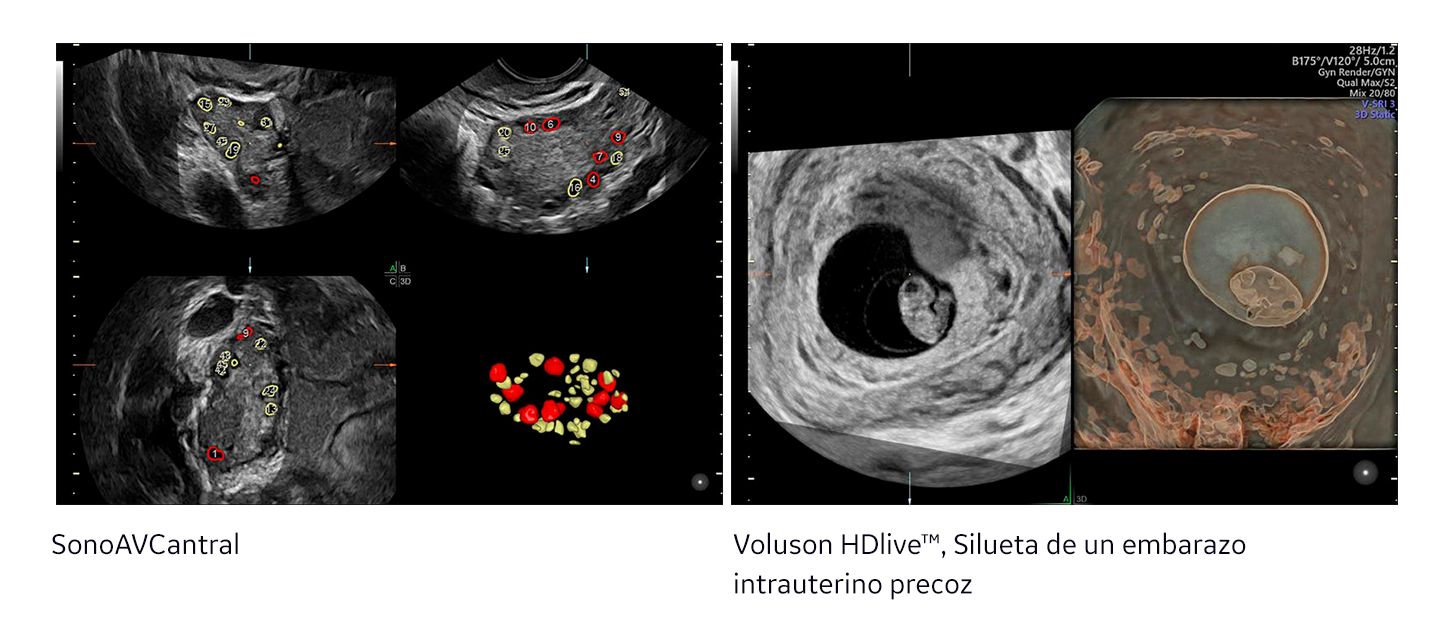

R: Los sistemas de Voluson proporcionan la información crítica que los especialistas en reproducción necesitan para la evaluación, FIV y el embarazo temprano. Por ejemplo, durante la fase de ‘evaluación’, la avanzada tecnología de Voluson permite la visualización del plano coronal, ayudando a localizar la posible patología y evaluar la forma del útero. Utilizando SonoAVC™ antral, el doctor puede evaluar el recuento de folículos antrales de manera eficiente para estimar la reserva de ovárica. Durante la etapa de FIV, SonoAVC™ folicular mejora la eficiencia y la Reproducibilidad del volumen folicular para controlar eficientemente la estimulación y determinar el momento óptimo para la recuperación de ovocitos. Y las imágenes en 2D de alta calidad de Voluson son críticas para realizar la recuperación de óvulos y la transferencia de embriones. Una vez que el embrión ha sido transferido, la imagen de Voluson es utilizada para evaluar si un embarazo viable se puede ver.